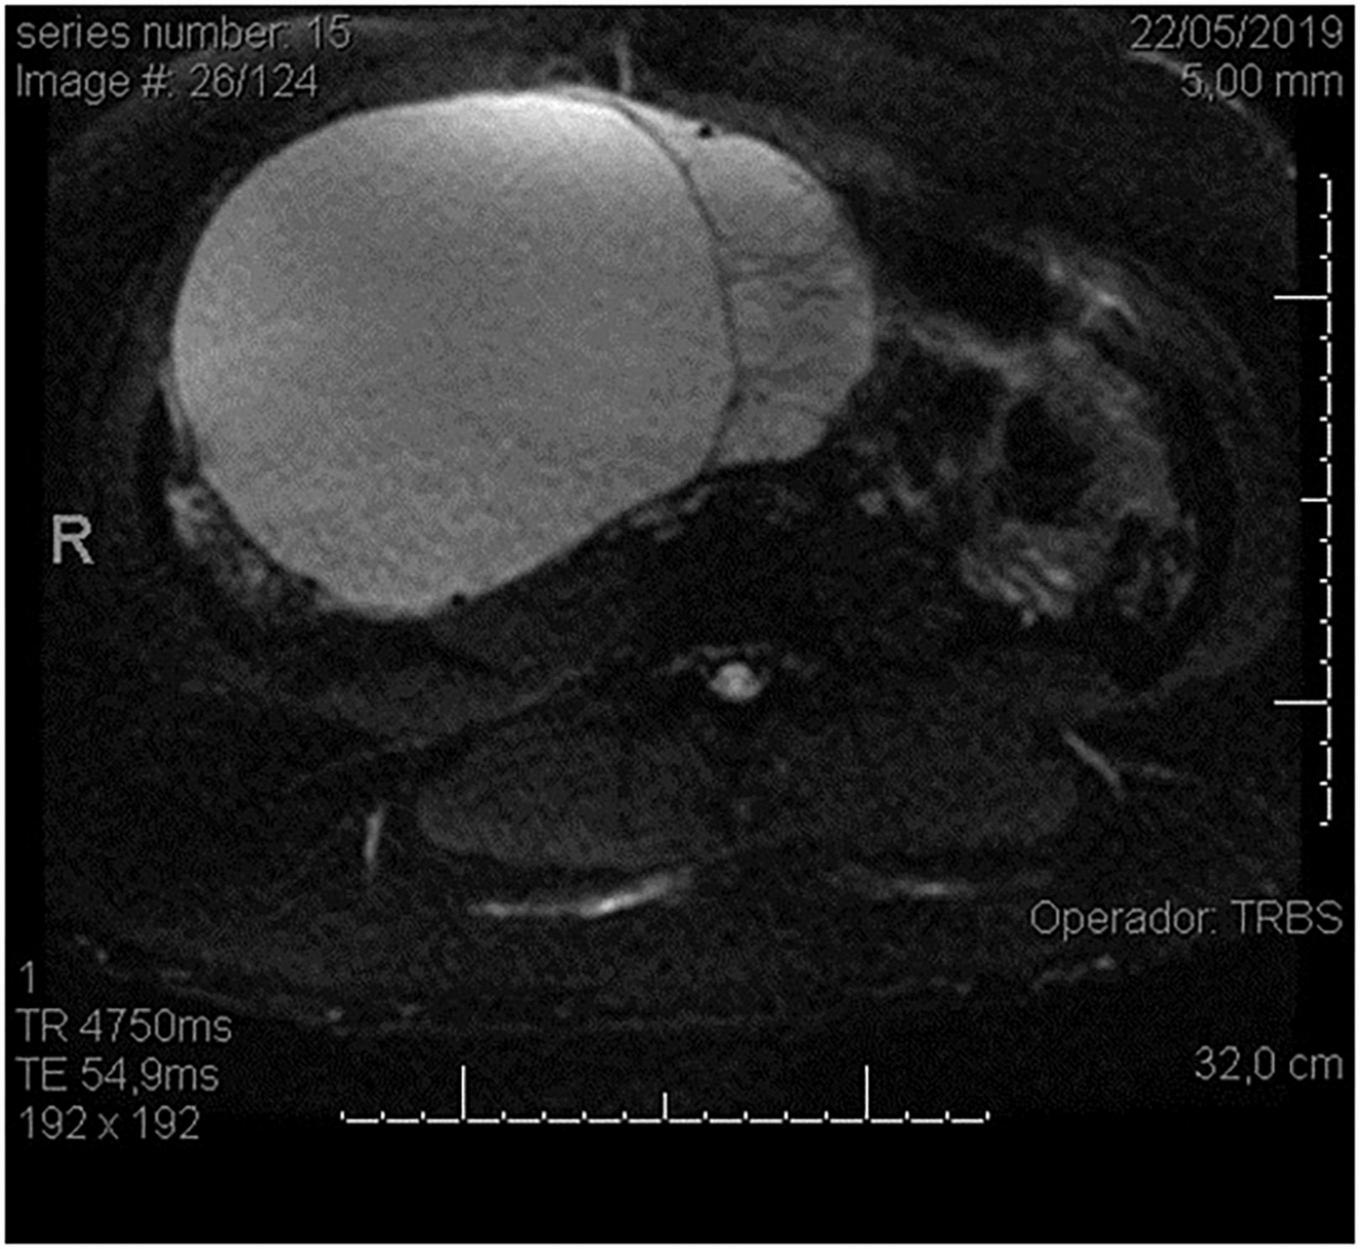

FIGURE 2

Magnetic resonance (MR) image showing a large ovarian cystic formation on the right in axial view.

Our patient was a 29-year-old woman, gravida 3, with a history of cesarean deliveries. During gynecological follow-up for contraception, a nodular image was identified in the right ovary on pelvic ultrasonography (USG) performed in February 2019. The cyst was solid, with regular thin walls and heterogeneous, thick content, without vascular expression on Doppler. It measured 14.5 cm×14 cm×10.4 cm (Figure 1). Due to the size of the tumor, surgical removal was indicated. However, in March 2019, during the preoperative examination, the patient was found to be pregnant and she was referred to our high-risk prenatal care. Pelvic USG was performed at that time and showed a topical pregnancy with a viable embryo at 7 weeks and 4 days, and solid-cystic formation in the right adnexal region. The serum dosage of carbohydrate antigen-125 (CA125) was 54.2 U/mL (normal, up to 35 U/mL). Additionally, magnetic resonance imaging (MRI) of the pelvis was performed on 22 May 2019 (Figure 2), confirming a voluminous, complex, multiloculated, right ovarian cystic formation with some areas of hemorrhagic content, measuring 17 cm×12 cm×18 cm (1920 cc estimated volume), without a fat component, compatible with a primary ovarian lesion. Due to the dimensions and characteristics of the tumor, an exploratory laparotomy was performed during pregnancy once the patient had consented. At 14 weeks and 5 days of pregnancy, on 5 June 2019, she underwent a right salpingo-oophorectomy (Figure 3), with no implants during revision of peritoneal cavity, and peritoneal fluid was collected for cytology without clinical and surgical complications. The pathology evaluation (AP) showed (Figure 4) an intestinal-type mucinous adenocarcinoma with an infiltrative stromal invasion pattern, moderately differentiated (G2) with an intact capsule, absence of neoplastic cells on the surface, and restriction of the tumor to the ovary. The ovary weighed 2,721 g, measured 20 cm×17 cm×12 cm. The cytology of the abdominal cavity was negative for neoplastic cells. Immunohistochemistry of the surgical specimen (06/05/2019) showed cytokeratin 7 (CK7)-, CK20-, and caudal type homeobox 2 (CDX2)–positive phenotypes. Based on these findings, considering stage IA (FIGO) of the disease and the pregnancy, after a joint evaluation with the oncology team of the Institute of Cancer of São Paulo (ICESP), an expectant approach was chosen, and the patient did not receive chemotherapy nor taken up for surgery during the pregnancy. In addition, to investigate the gastric or intestinal origin of the tumor, endoscopy and colonoscopy were performed at 18 weeks, both of which were normal. At 28 weeks of gestation, she developed a mild, pregnancy-specific, hypertensive disease that was initially controlled with diet, followed by 750 mg/day of methyldopa. The patient developed no other complications during prenatal care. At 40 weeks, elective cesarean section was performed (28 November 2019). The live newborn (NB) was a male with scores on the appearance, pulse, grimace, activity, and respiration (Apgar) scale of 8–9–10, and weighing 3,460 g. Intercurrent intraoperative uterine hypotonia was reversed with oxytocin, uterine massage, and 800 μg of misoprostol. Intraoperative evaluation of the abdominal cavity was performed during delivery with no evidence of tumor recurrence. The patient did well in the postoperative period and was discharged after 3 days. After delivery, the patient was followed up in the oncology department at ICESP with careful outpatient clinical examination and imaging tests (CT scans of the chest, abdomen, and pelvis). No evidence of disease recurrence was found.